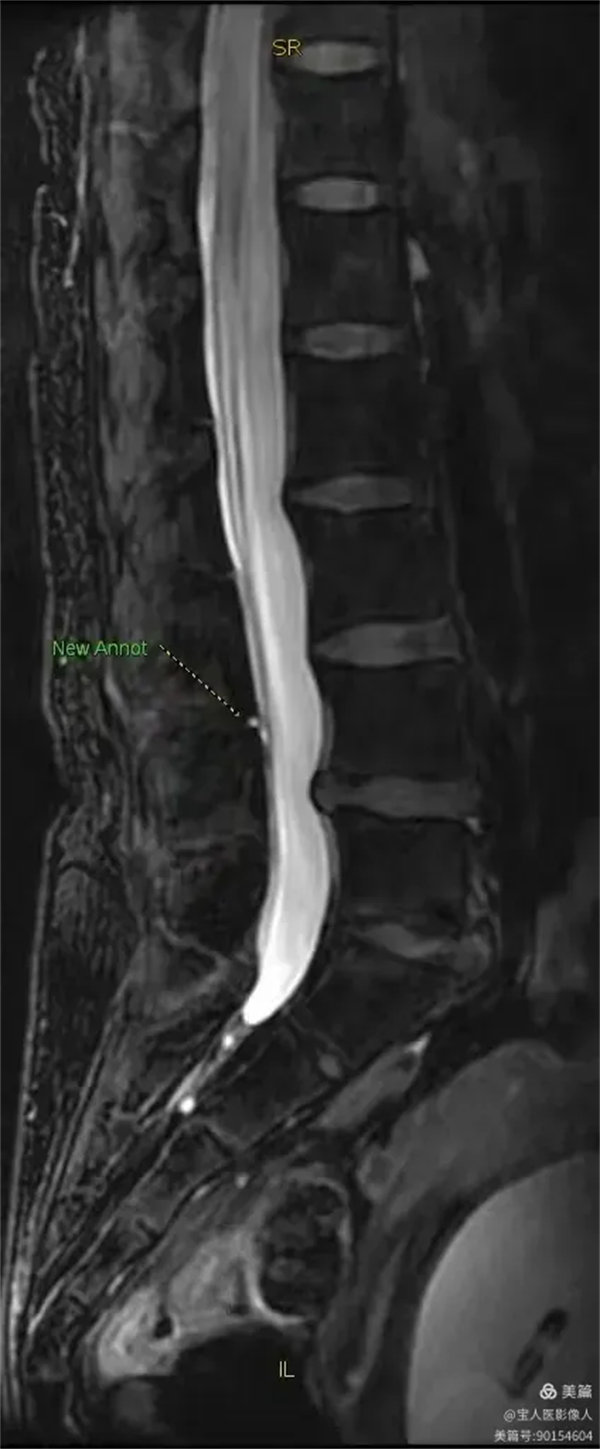

最大密度侧面图,显示腰段硬膜囊内脑脊液(高信号)。

最大密度侧面图,显示腰段硬膜囊内脑脊液(高信号),前方的椎间盘受压弧形凹陷,后方的局部膨出。